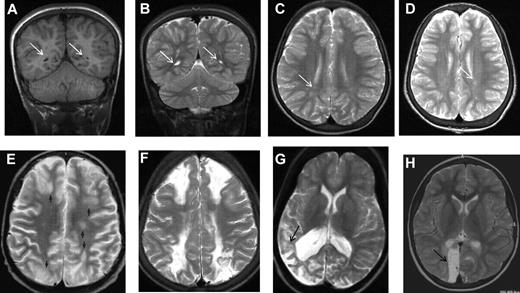

MRI in sickle cell disease. (A) Coronal T1-weighted MRI, (B) coronal T2-weighted MRI, and (C-H) axial T2-weighted MRI in patients with homozygous SCA. (A-C) Silent cerebral infarction (white arrows) in the parietal white matter in a 10-year-old girl with headache. (D) Three years later, there is progressive atrophy on MRI in the context of intermittent ataxia and squint. (E-H) Four cases associated with acute illness. (E) Silent cerebral infarction (black arrows) in the watershed regions between the anterior, middle, and posterior regions, including the deep white matter, in a patient who had previously had posterior reversible encephalopathy syndrome in the context of cyclosporine treatment for nephrotic syndrome. (F) Bilateral watershed infarction in a child who had seizures in the context of a facial infection. Motor examination was normal but his IQ was reduced by 30 points compared with premorbid testing. (G) Encephalomalacia after sagittal sinus thrombosis secondary to pneumococcal meningitis. (H) Occipital infarction after acute chest crisis. A homonymous visual field defect was detected after the infarct was noted on MRI.

In the first systematic study of SCI in adults with SCA, Vichinsky et al used a definition of a minimum of 5 mm signal hyperintensity in the T2-weighted image,9 but to be included, lesions also had to show corresponding hypointensity on the T1-weighted image (Figures 1E, 2A). Normal adults typically accumulate T2 hyperintensities as they age, but children do not. This more restrictive definition of SCI and the distinction from encephalomalacia and atrophy (Figures 1H, 2D-H) parallels the descriptions used in general populations of asymptomatic elderly adults with SCI.10

In another study of 50 adults, including 4 with overt stroke, Silva et al found that leukoencephalopathy was the most common abnormality (48%),25 followed by atrophy (28%; Figures 1H, 2D), encephalomalacia (6%; Figure 2F-H), and lacunes (Figure 1E-H; 4%). Vichinsky et al completed brain MRI in adults with SCA as an initial component of a randomized trial.9 Entry into the study required that the participants had a baseline hemoglobin concentration below 10 g/dL without any history of stroke or focal neurologic deficits, known brain imaging abnormalities, serious cognitive impairment, or evidence of depression. Nevertheless, in this group of highly selected adults with SCA, SCI, referred to as lacunar infarction, was present in 13% of the surveillance MRIs compared with 2% of the ethnic and age-matched controls without SCA. In contrast, white matter lesions occurred in 15% of individuals with SCA and 7% of controls, atrophy was seen in 23% of patients and 16% of controls, and a cortical infarct was detected in one individual with SCA and one control. The difference in SCI prevalence compared with the published pediatric cohorts may be related to either (1) the highly selected group of well-functioning adults with SCA or (2) a subtle, but important, variation in the definition of SCI, related either to the difference in minimum size (5 mm vs 3 mm) or to the requirement for T1 hypointensity, as well as T2 hyperintensity in the adult study. A longitudinal study that includes children, adolescents and adults with SCA is required to determine the true natural history and sequelae of SCI. Based on the high prevalence of SCI in adults with SCA, screening MRI of the brain may be considered standard care, despite the lack of evidence-based therapy, because detection of SCI may help facilitate employment or vocational options along with realistic expectations for the management of a complex chronic illness. Ultimately, better data are required to understand the clinical course and relevance of SCI in adults with SCA.